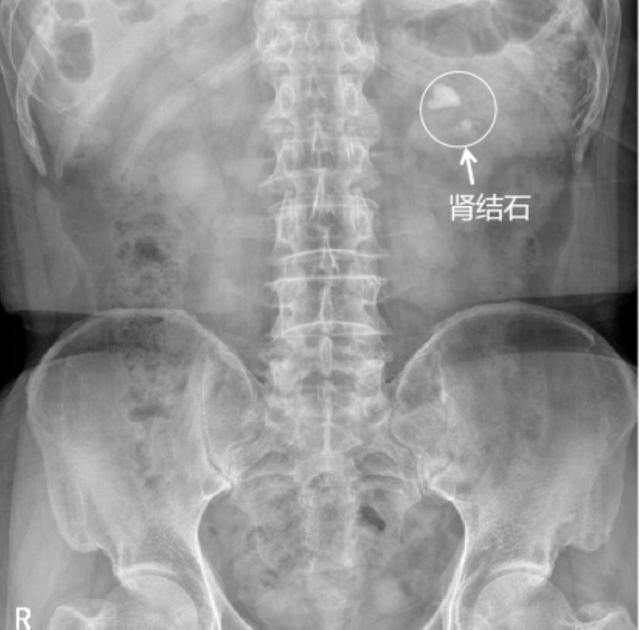

患者丁叔,诊断:左肾多发结石并左肾积水。

术式:输尿管软镜联合负压吸引碎石取石术。

▲手术前